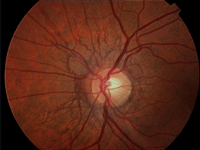

La manifestación ocular más frecuente consiste en la presencia de escleróticas azules. Estas, se asocian con la reducción de rigidez escleral (adelgazamiento de las fibras que componen la esclerótica lo que permite la transparencia de los vasos coroideos) (

Figura 1).

Figura 1. Escleras azules en un paciente con osteogénesis imperfecta.

Este signo es más evidente con luz natural.